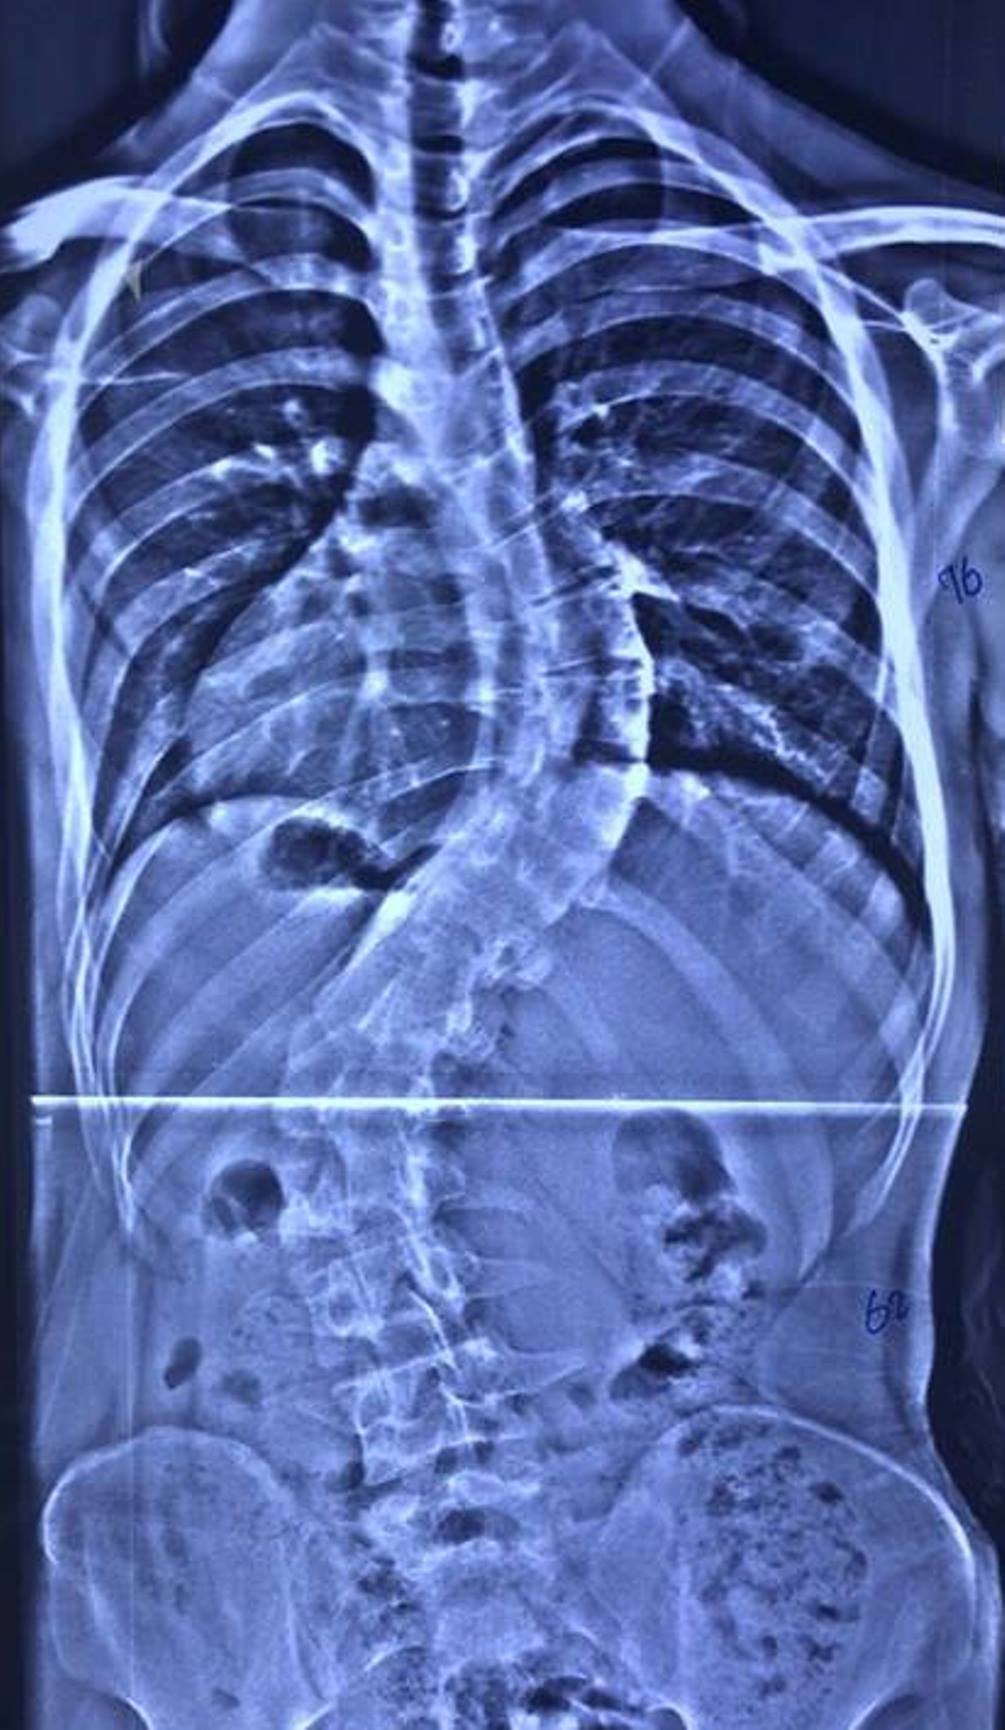

تعديل العمود الفقري لمريضة ستينية بعملية نوعية

أعلن فريق طبي في مستشفى الكفيل التخصصي بكربلاء، نجاحه بعملية تعديل جنف العمود الفقري لمريضة ستينية.

وقال إختصاصي جراحة العمود الفقري بالمستشفى الطبيب اللبناني، دكتور عامر السبعلي، في حديث صحافي، إن فريقنا الطبي نجح بعملية تعديل جنف العمود الفقري (إنحراف وتحدب العمود الفقري) لمريضة تبلغ من العمر (63) عاما، مبيناً إن الجنف بنسبة (35%)، وإن المريضة تعاني من تضييق في مجرى الدودة يرافقه آلام حادة جعلتها غير قادرة على ممارسة حياتها بشكل طبيعي.